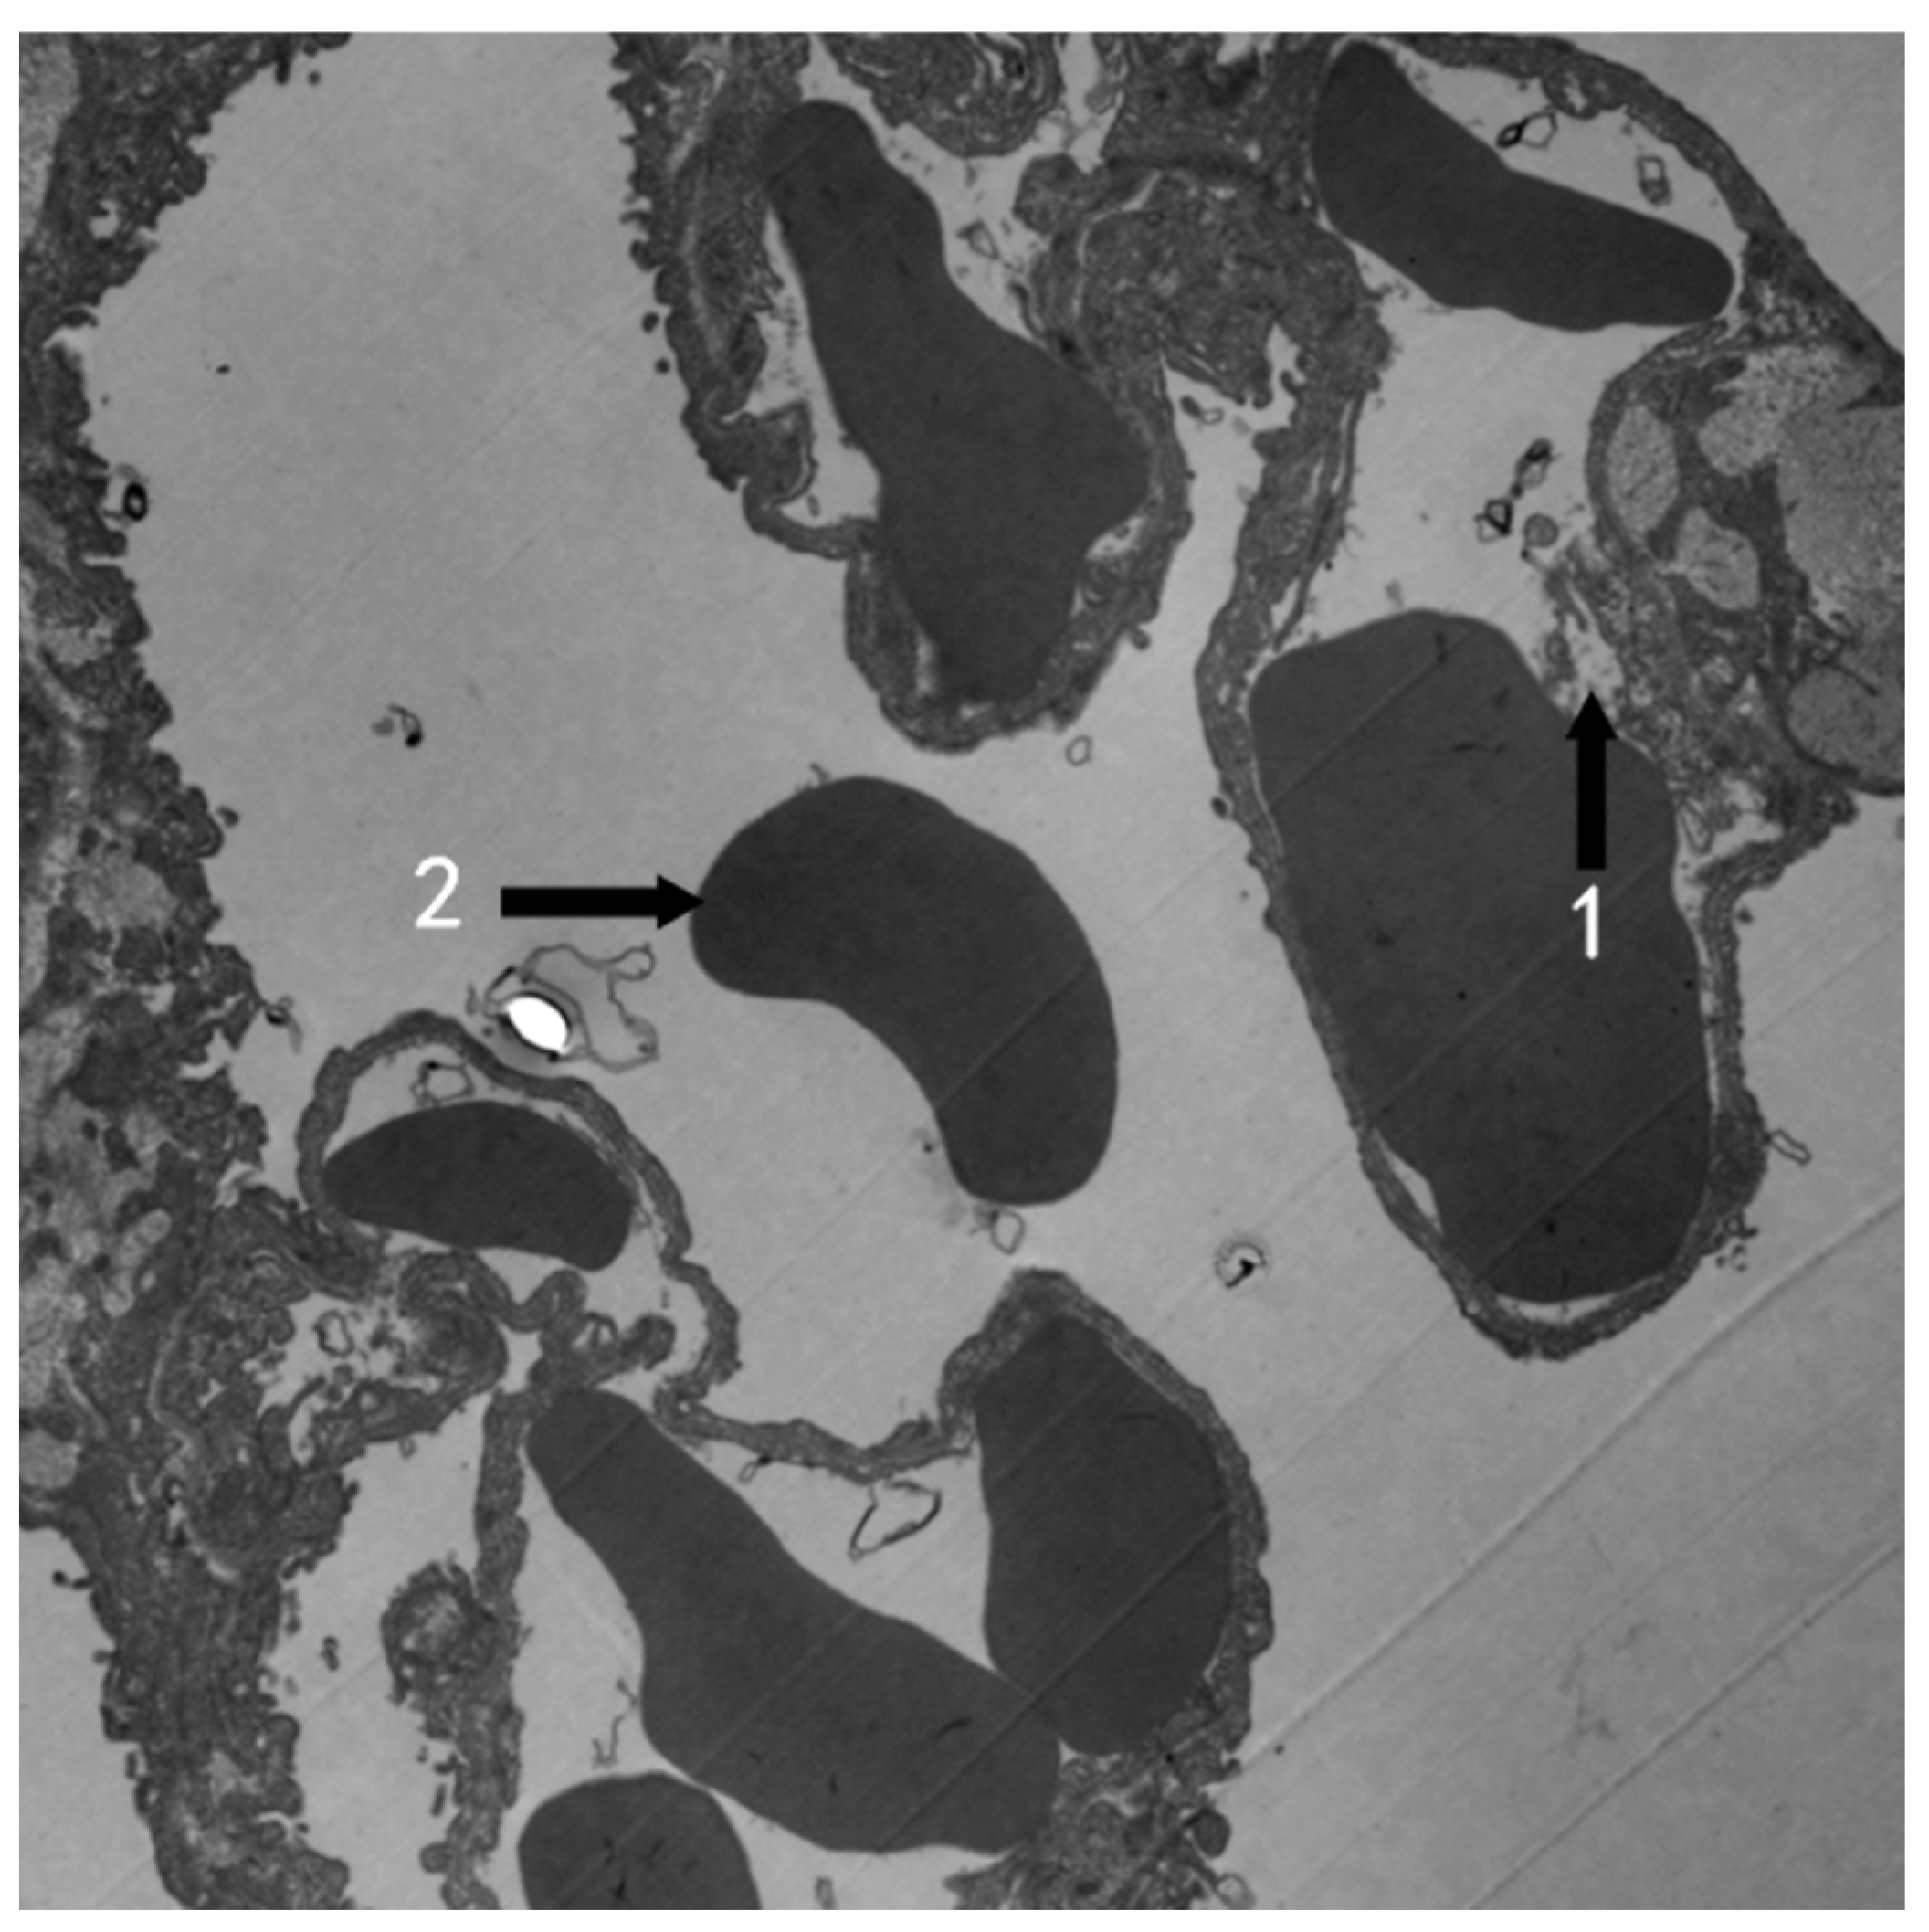

3.2. TEM Observation